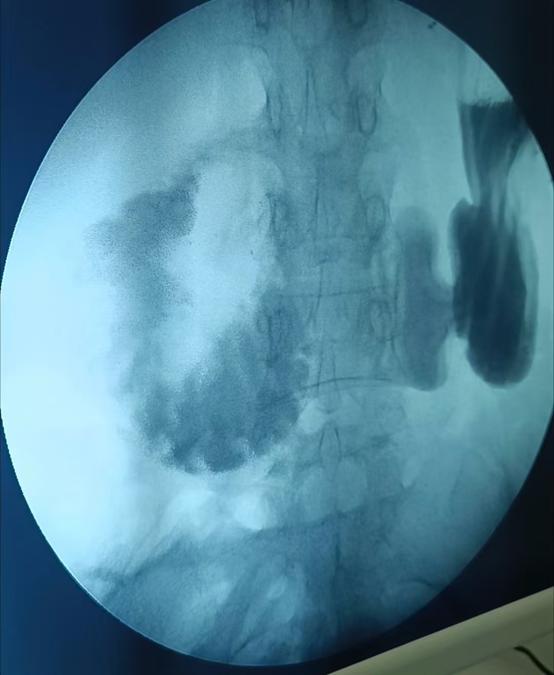

經(jīng)過(guò)一系列檢查,腹主動(dòng)脈CTA及上消化道造影檢查揭示了病因——腸系膜上動(dòng)脈卡壓綜合征。

術(shù)后7天,復(fù)查上消化道造影顯示十二指腸空腸吻合口愈合良好、通暢,開始正常流質(zhì)飲食了。手術(shù)后第9天,林女士順利康復(fù)出院,回歸到正常的生活軌道。